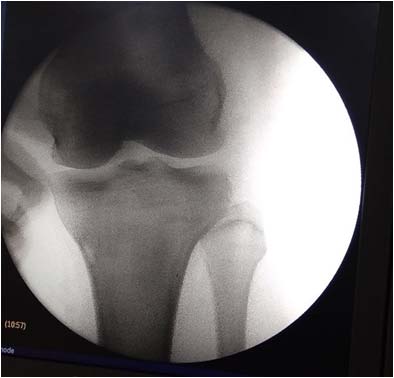

Case 1-A 50-year-old lady presented with pain in the left knee of one year duration. There was no improvement with conservative treatment in the form of anti-inflammatory medication and physiotherapy. X-ray of the knee showed calcification in the LCL region (Fig. 1a 1b). The technique of arthroscopic excision of calcification in LCL.

Under spinal anesthesia, the patient is placed in supine position with the limb held by thigh holder, so that the knee is in a hanging down position, making a flexion angle of 90 degrees. Standard anterolateral and anteromedial portals were made. The knee was then positioned into extension with arthroscope in the anterolateral portal. A needle was placed over lateral epicondyle under IITV guidance (Fig. 3). With the arthroscope in the anterolateral portal, the superolateral portal was made. Bands over the lateral gutter (Fig. 4 a) were cleared and then the arthroscope was moved inferiorly and posteriorly until the needle over the lateral epicondyle (Fig. 4 b) was visualized. A direct lateral portal, 1cm inferior and 1cm posterior to the lateral epicondyle with the knee in extension was made (Fig. 4 c and d). The calcific deposits in LCL were visualized (Fig. 4 e). The LCL and popliteus were dissected (Fig. 5), calcific deposits in the LCL was debrided by switching the arthroscope and shaver between the anterolateral portal and direct lateral portals. A small part of the LCL was shaved at the area of calcific deposit and all the deposit was squeezed out. Intactness of the LCL was confirmed with Varus stress test and the opening of the lateral joint was confirmed under IITV guidance (Fig. 6 a, 6b).

Looking at the safety of this portal, we performed an arthroscopic debridement of calcific deposit in LCL in 2 patients. Along with standard anterolateral, anteromedial portals, a superolateral portal was made. Through the superolateral portal, bands in the lateral gutter were shaved with arthroscopic shaver and then a 'direct lateral portal' was done 1cm inferior and 1cm posterior to lateral epicondyle to visualize the LCL. This portal is anterior to the anterior border of the fibula, so there is no risk of injury to the common peroneal nerve. Calcific deposits in the LCL were identified and debrided by switching the arthroscope and shaver between the anterolateral portal and direct lateral portals. Finally, intactness of LCL was confirmed by varus stress test and recorded with C-arm. Postoperative X-ray (Fig. 8 a,b) shows the completeness of evacuation of calcification from the lateral side of the knee.